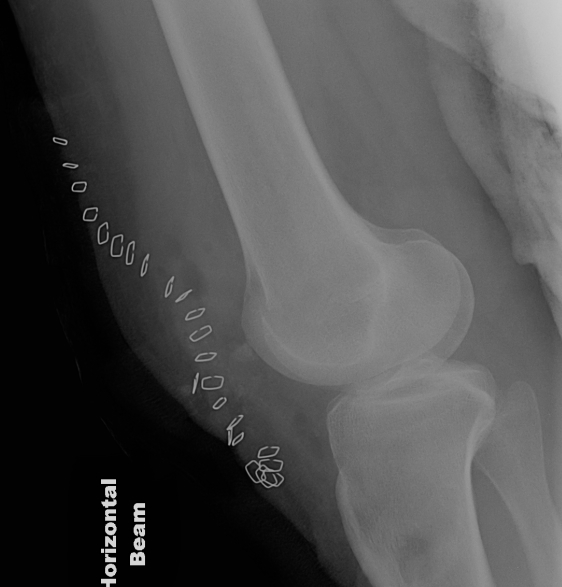

Types

1. Vertical

2. Transverse

3. Burst / Stellate

1. TBW

2. Cerclage wire +/- ORIF

- stellate fractures